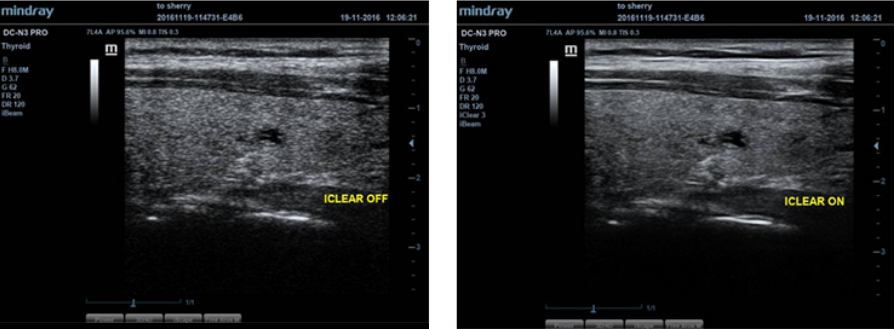

iClear?

Dapatkan peningkatan kualitas gambar berdasarkan deteksi struktur otomatis

- Batas Lebih Tajam & Kontinu.

- Keseragaman Jaringan.

- ŌĆśArea tanpa gemaŌĆÖ lebih bersih.